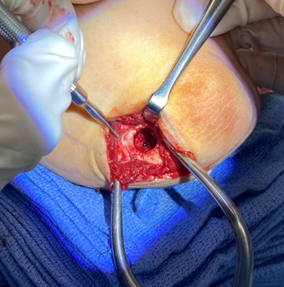

The damaged cartilage and underlying bone is removed using appropriate sizers

A size-matched plug of cartilage is harvested from the non-weightbearing portion of the knee and prepared for transfer to the elbow

The cartilage plug is contoured and placed within the elbow defect completing the cartilage transfer